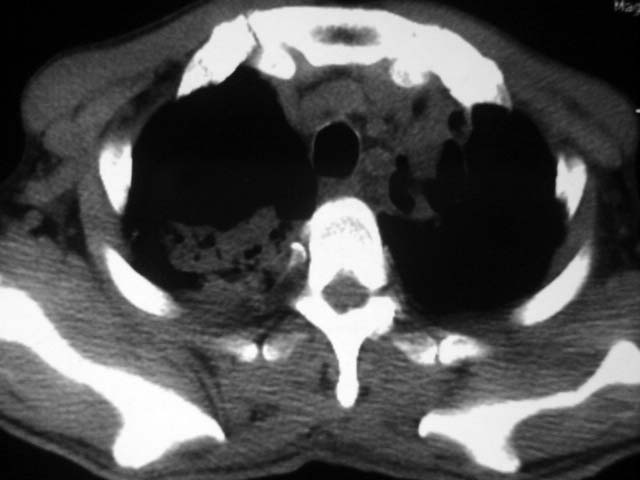

男,52岁,发热2月,糖尿病史。

抗结核治疗irpz方案,血糖未治疗,空腹15.9左右。症状无好转,左胸痛。

复查ct

2、双肺见多发片状及结节状高密度影,大多数病灶中心均见“空泡征”。

3、纵隔内淋巴结肿大。

结果:两肺继发性肺结核并曲霉菌感染。